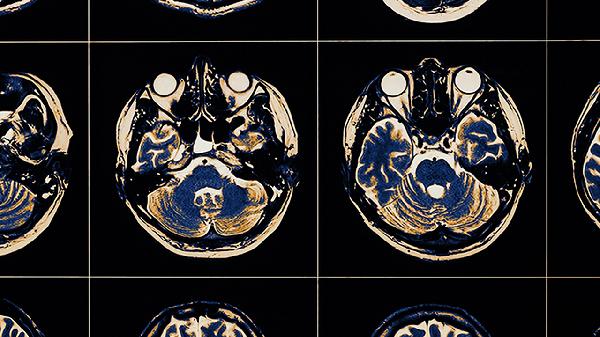

脑血栓的前兆主要有突发单侧肢体无力、言语不清、头晕目眩、视物模糊、短暂意识丧失等症状。脑血栓通常由动脉粥样硬化、高血压、糖尿病、房颤、血液高凝状态等因素引起,可通过溶栓治疗、抗血小板聚集、控制基础疾病等方式干预。若出现上述症状需立即就医。

突发单侧上肢或下肢无力是脑血栓的典型前兆,可能与大脑中动脉供血区缺血有关。患者常表现为持物不稳、行走拖沓,严重时可能出现偏瘫。此类症状多由动脉斑块脱落堵塞血管导致,需通过头颅CT或MRI确诊。急性期可遵医嘱使用阿替普酶注射液进行静脉溶栓,恢复期可服用阿司匹林肠溶片预防复发,同时配合血塞通软胶囊改善脑循环。